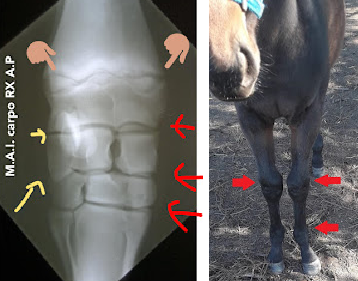

SOBRECAÑAS EN EL CABALLO

"No exija a un caballo con inflamación de cañas, podría generar lesiones muy graves que afectarían seriamente el futuro deportivo."